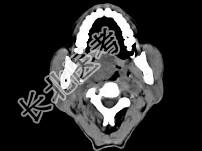

- 多项选择题男性,57岁, 睡觉打鼾,近来加重, CT扫描如图所示,请选择正确的描述和答案  (    )

- A、鼻咽腔偏右侧可见类圆形软组织块影

- B、肿块内密度尚均匀,其上方见较多钙化影

- C、肿块边缘大部清楚,邻近结构未见明显受侵

- D、考虑为鼻咽癌

- E、考虑为鼻咽部多形性腺瘤